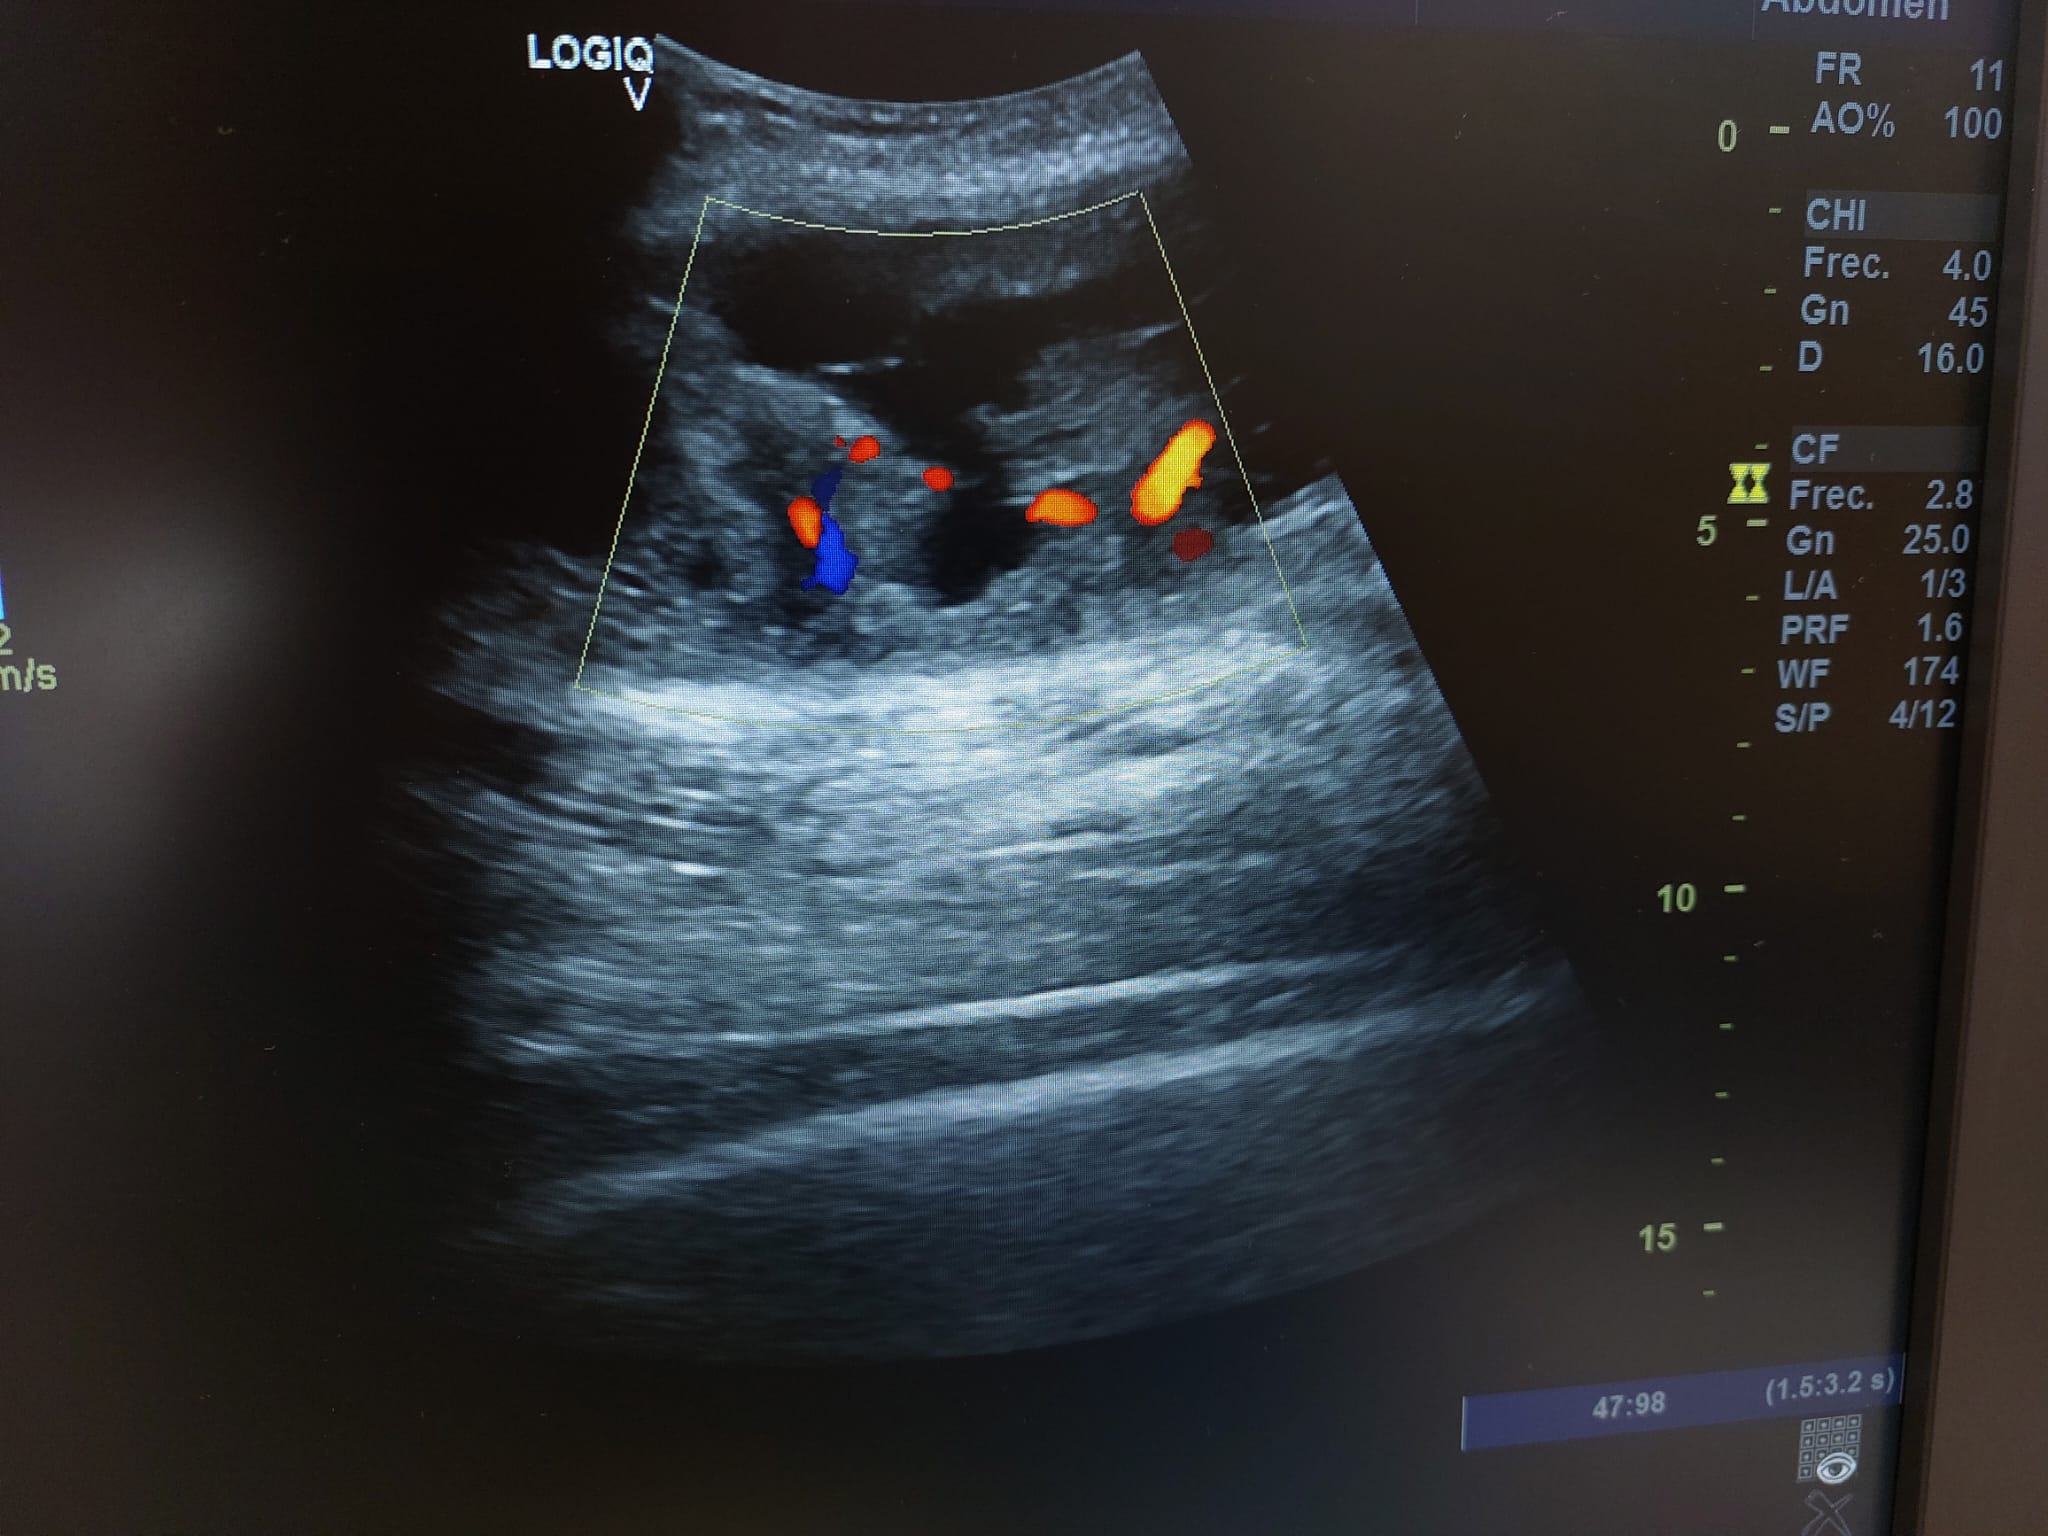

Se realiza ecografía observando colección anecoica a nivel muscular compatible con hematoma organizado, de aproximadamente 7 x 4 cm.

En el seguimiento se observa evolución tórpida sin mejoría clínica y en la ecografía de control se observa aumento notable de tamaño respecto al previo, estructura heterogénea de imagen anecoica con septos internos. Se aprecia edema intramuscular perilesional y captación al activar el Doppler. Se plantea la posibilidad de un hematoma sobreinfectado o, debido a su importante crecimiento, una probable etiología neoplásica. Tras hallazgos descritos en consulta, COT solicita de forma urgente la realización de RNM y biopsia de la lesión. Posteriormente, el resultado de las pruebas complementarias confirman diagnóstico de sarcoma histiocítico.